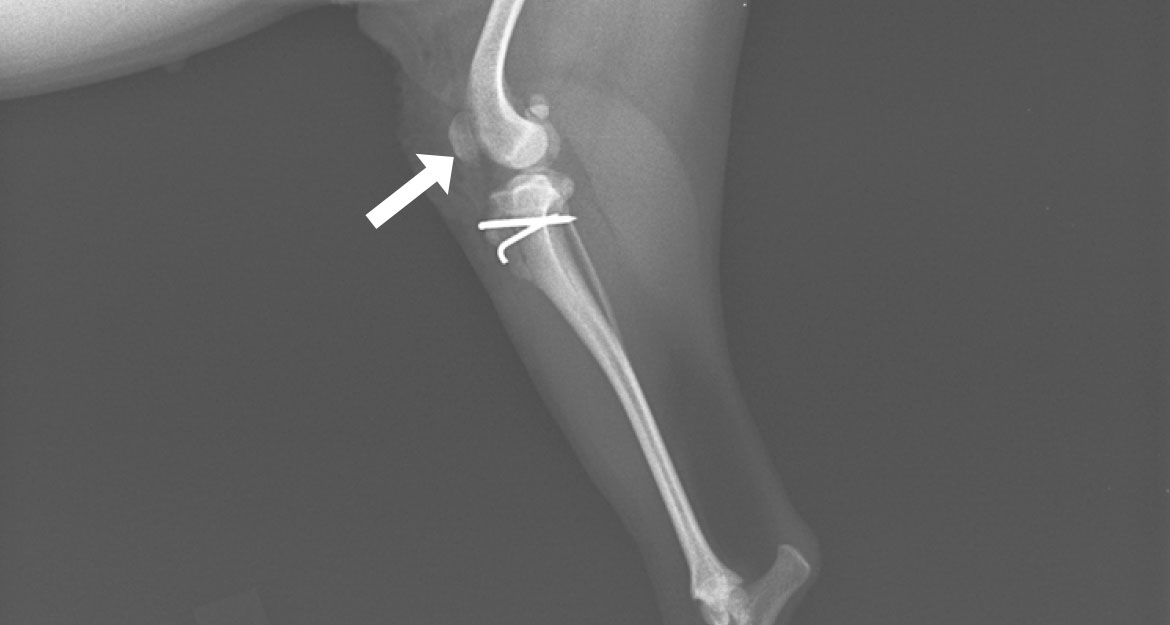

脛骨粗面転位術

けいこつそめんてんいじゅつ

膝関節のパーツが本来の配置・配列になるよう縦軸を矯正。

成長期に脱臼が起きると、膝蓋骨と膝蓋靱帯に引っ張られる形で脛骨もねじれます。その状態で成長すると、脛骨粗面(膝蓋靭帯が付着しているザラザラした部分)がまっすぐ前を向かず、内向きまたは外向きで定着してしまいます。滑車造溝術で溝を造り、脱臼を整復しても、脛骨のねじれをそのままにしておくと、脛骨粗面に付着している膝蓋靭帯が膝蓋骨を引っ張り戻すことになり、再脱臼のリスクが高くなります。

脛骨粗面転移術とは、粗面を膝蓋靭帯が付着したままの状態で骨切りし、大腿骨の溝、膝蓋骨、脛骨粗面が本来の縦一直線で並ぶ正しい位置まで移動させ、ピンで固定させる手術です。膝蓋骨脱臼において、滑車造溝術と組み合わせて施されることの多い術式になります。